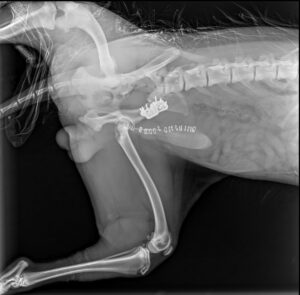

Kolejne zespolenie kości biodrowej po pojedynczej osteotomii miednicy – tym razem z zastosowaniem klamry kostnej w celu zwiększenia wytrzymałości.

Zachęcamy również do zapoznania się z naszą ofertą płytek do osteotomii miednicy – dostępne w systemie 2.4/2.7, 3.5 oraz 5.0!